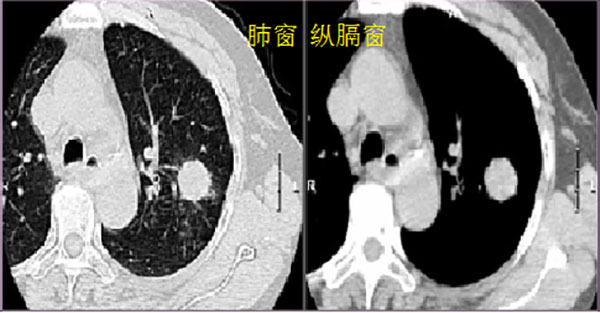

CT的成像原理是依机体组织的密度不同,呈现出来的颜色不同,以此来分辨相应组织的形态。密度越低的组织颜色越趋于黑色,如肺泡、气管管腔、胃泡、肠腔等空腔组织为空气密度,显纯黑色;密度越高的组织颜色越趋于白色,如骨骼、组织内钙化灶,呈亮白色;人体内的绝大多数组织器官的密度则在空气密度和骨骼密度之间,呈不同程度的灰色。但在同一张片子中,因人眼对颜色色差的分辨能力有限,如果按照从空气密度到骨骼密度这样从白到黑均匀呈现所有的组织差异,反而会使得有些需要区分的组织显示出的色差很微小,不利于阅片。所以在洗片子时我们会对每张片子上的灰阶范围进行调整,胸部CT的片子我们通常会出两套,一套叫做“肺窗”,一套叫做“纵膈窗”,如下图所示:

顾名思义,肺窗是为了更好地观察肺实质的情况,集中呈现肺实质密度(也就是较低密度)附近的色差变化,在这种情况下,密度稍高一些的组织,则已经显影为白色,比如肺部感染的炎性渗出、肺部肿瘤、心脏、血管等等,全都像骨头一样呈现白色。纵膈窗则是为了更好地观察纵膈内的心脏、血管、食管、淋巴结等组织的情况,集中呈现软组织密度附近的色差变化,在这种情况下,软组织密度的组织呈现深浅不一的灰色,阅片时可以在一定程度上区分他们的密度是否均匀,而对于密度较低,接近肺实质密度的组织则都像空气一样呈现黑色。